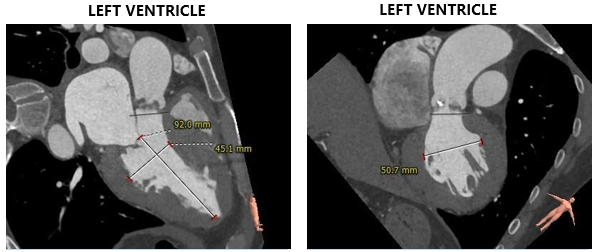

术前CT评估

主动脉根部测量

CT特点:三叶式主动脉瓣,瓣叶轻度钙化,钙化主要位于无窦瓣叶边缘及左右窦交界处,瓣叶显著增厚伴左右窦部分融合;瓦氏窦、窦管交界内径偏小,升主动脉内径可;右冠开口高度可,左冠偏低,瓣叶冗长;非横位心。

瓣上测量

瓣上测量:瓣叶钙化较轻、增厚显著,瓣膜锚定难度稍高;左右窦交界纤维性融合存在一定限制。